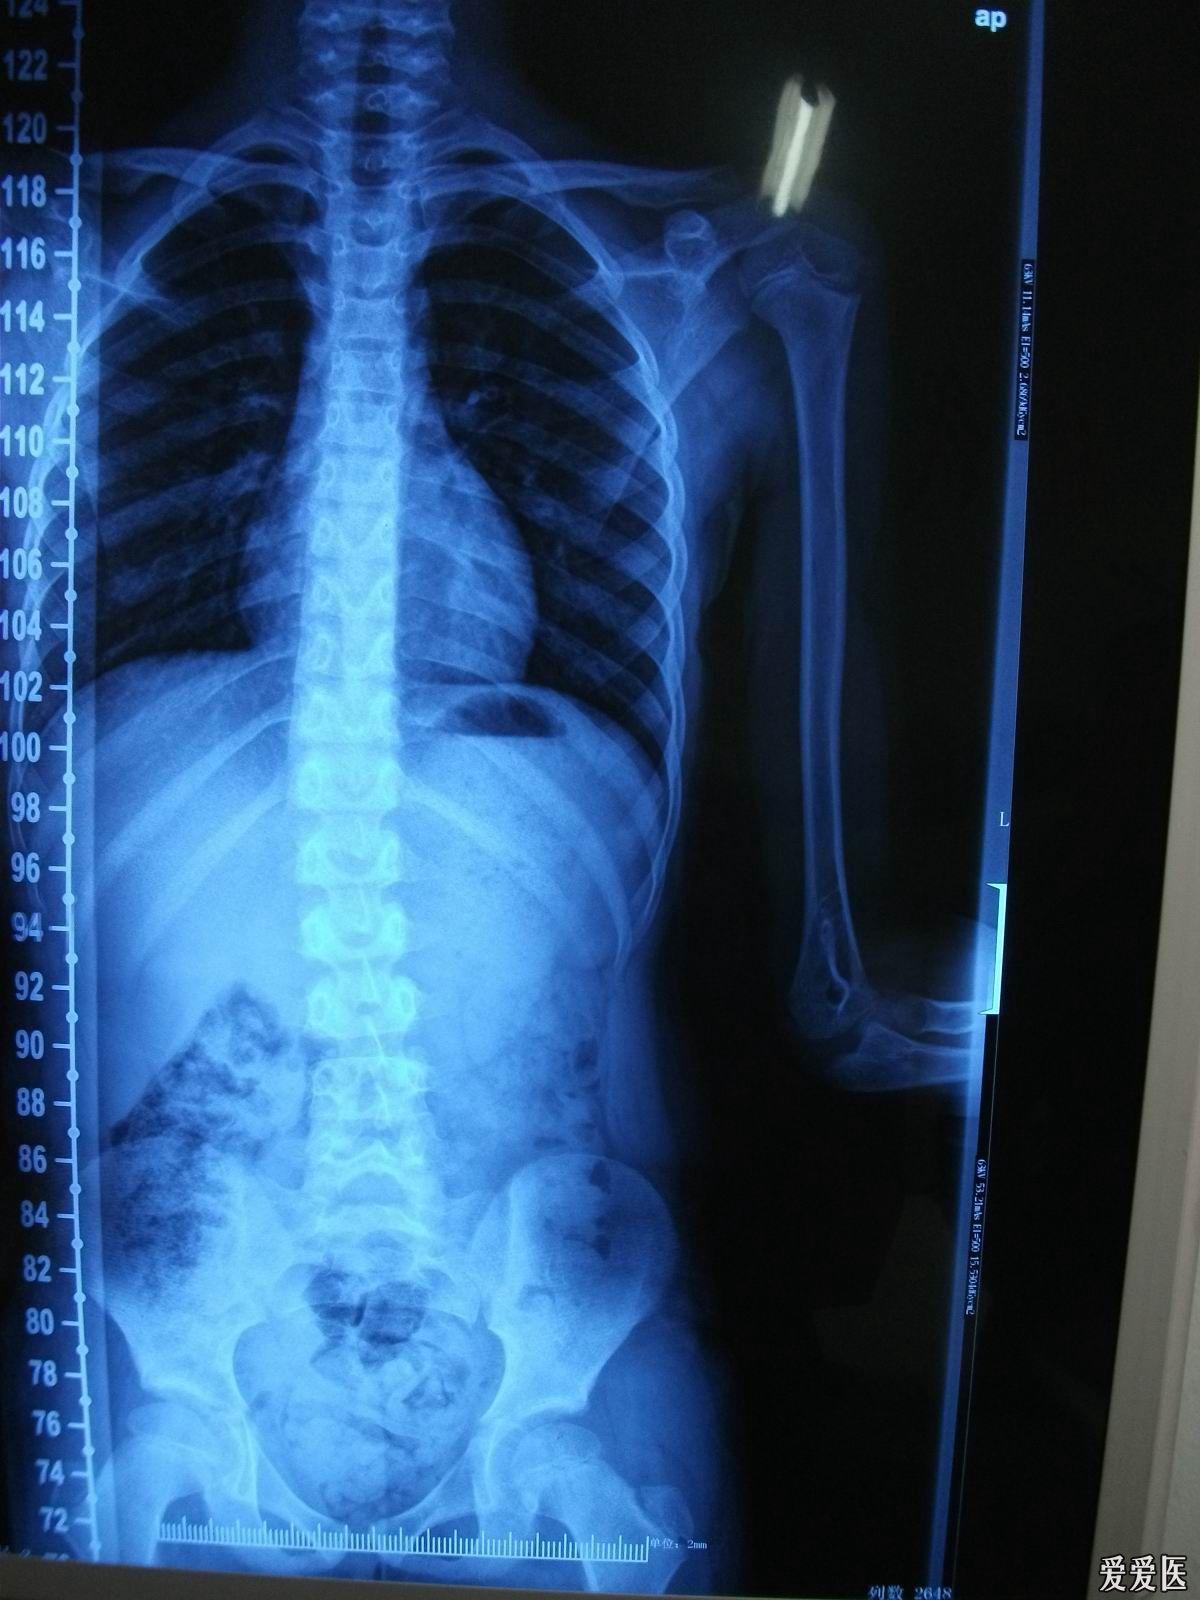

脊柱片子,脊柱图片

各位老师看一下片子,是否有脊柱侧弯

脊柱侧弯